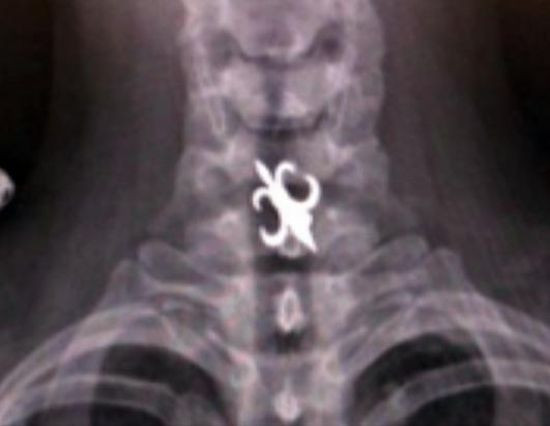

Radiografii terifiante: foarfece in cap, cuie in gat si furculite in mana

Surublenite infite in cap, plamani "dotati" cu cuie sau laringe "presarat" cu foarfece. Sunt numai cateva dintre cele mai ingrozitoare radiografii cu care s-au confruntat medicii de-a lungul timpului.

Iata mai jos o serie cu unele dintre cele mai "spectaculoase" radiografii.